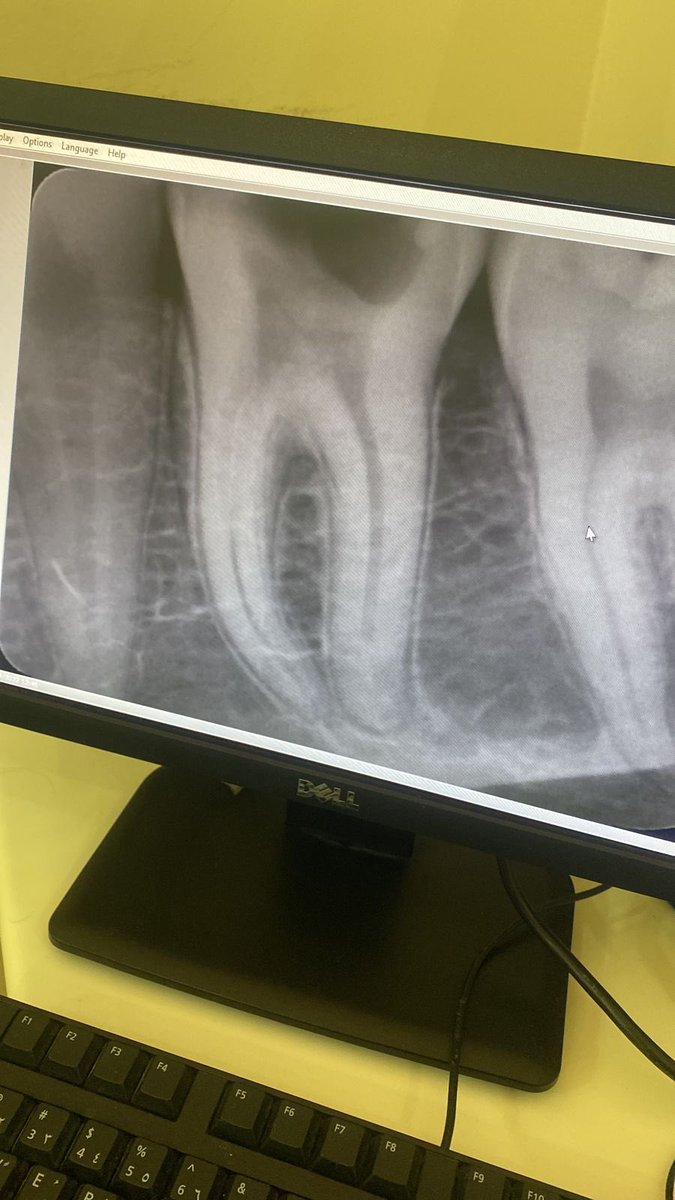

#47🦷

Dx:

Symptomatic irreversible pulpitis with symptomatic apical periodontitis

Tx:

RCT followed by TF